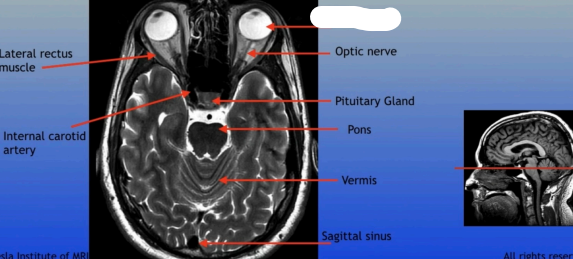

Lateral Rectus Muscle

Internal Carotid Artery

Optic Nerve

Pituitary Gland

Pons

Vermis

Sagittal Sinus